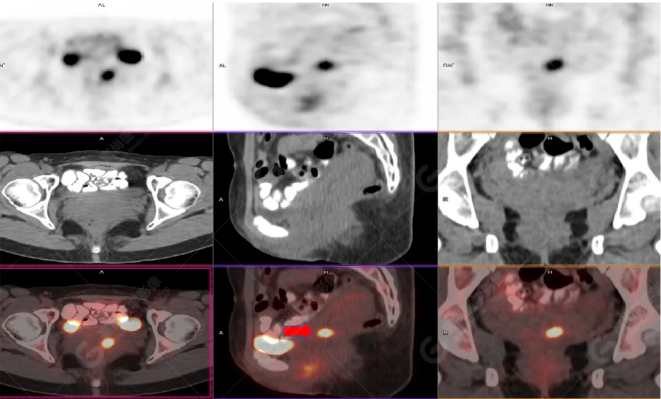

PET/CT影像圖

左胸一后肋溶骨性骨質(zhì)破壞,周?chē)檐浗M織形成,F(xiàn)DG代謝增高,SUVmax為10.9。

找到引起骨痛病灶,病因:原發(fā)?轉(zhuǎn)移?感染?

宮頸一片狀稍低密度影,F(xiàn)DG結(jié)節(jié)樣代謝增高,SUVmax為10.2。

最終診斷:宮頸癌伴肋骨單發(fā)骨轉(zhuǎn)移。